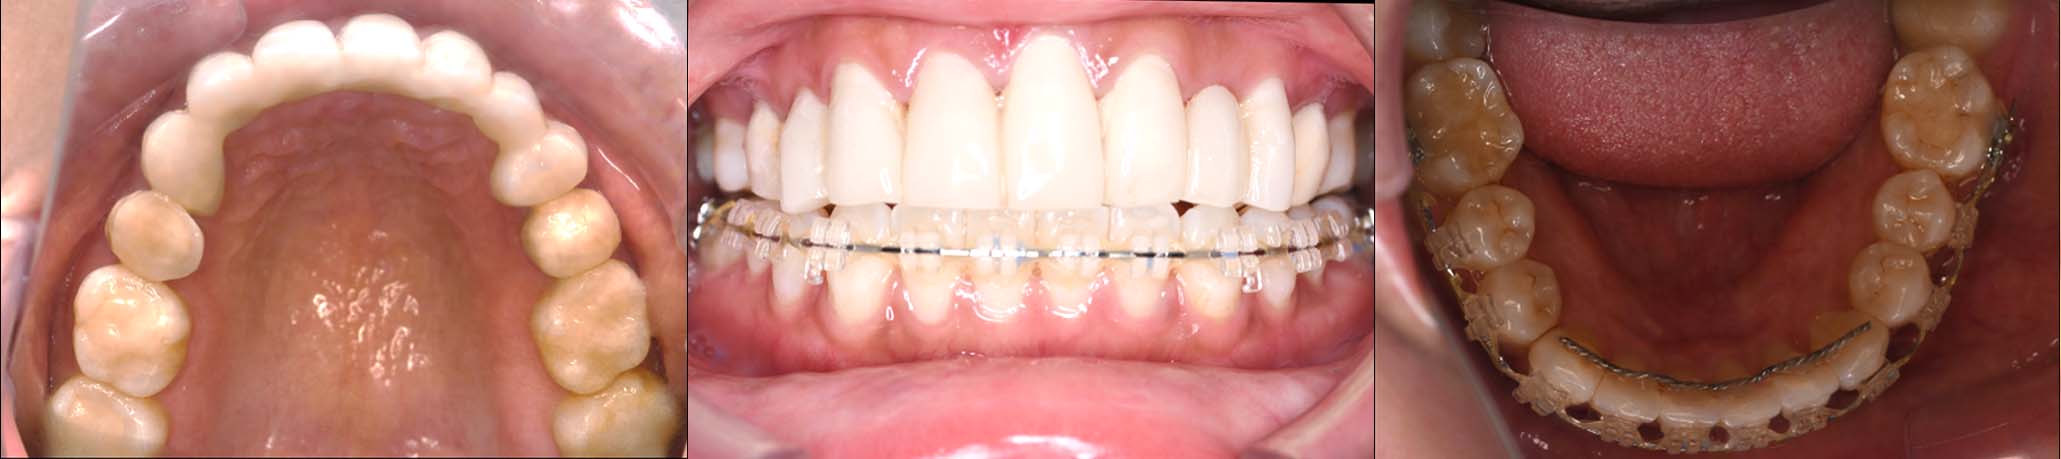

姿勢の変化

2024年 3月 初診時

2024年 10月10日

2025年 12月25日

顔貌の変化